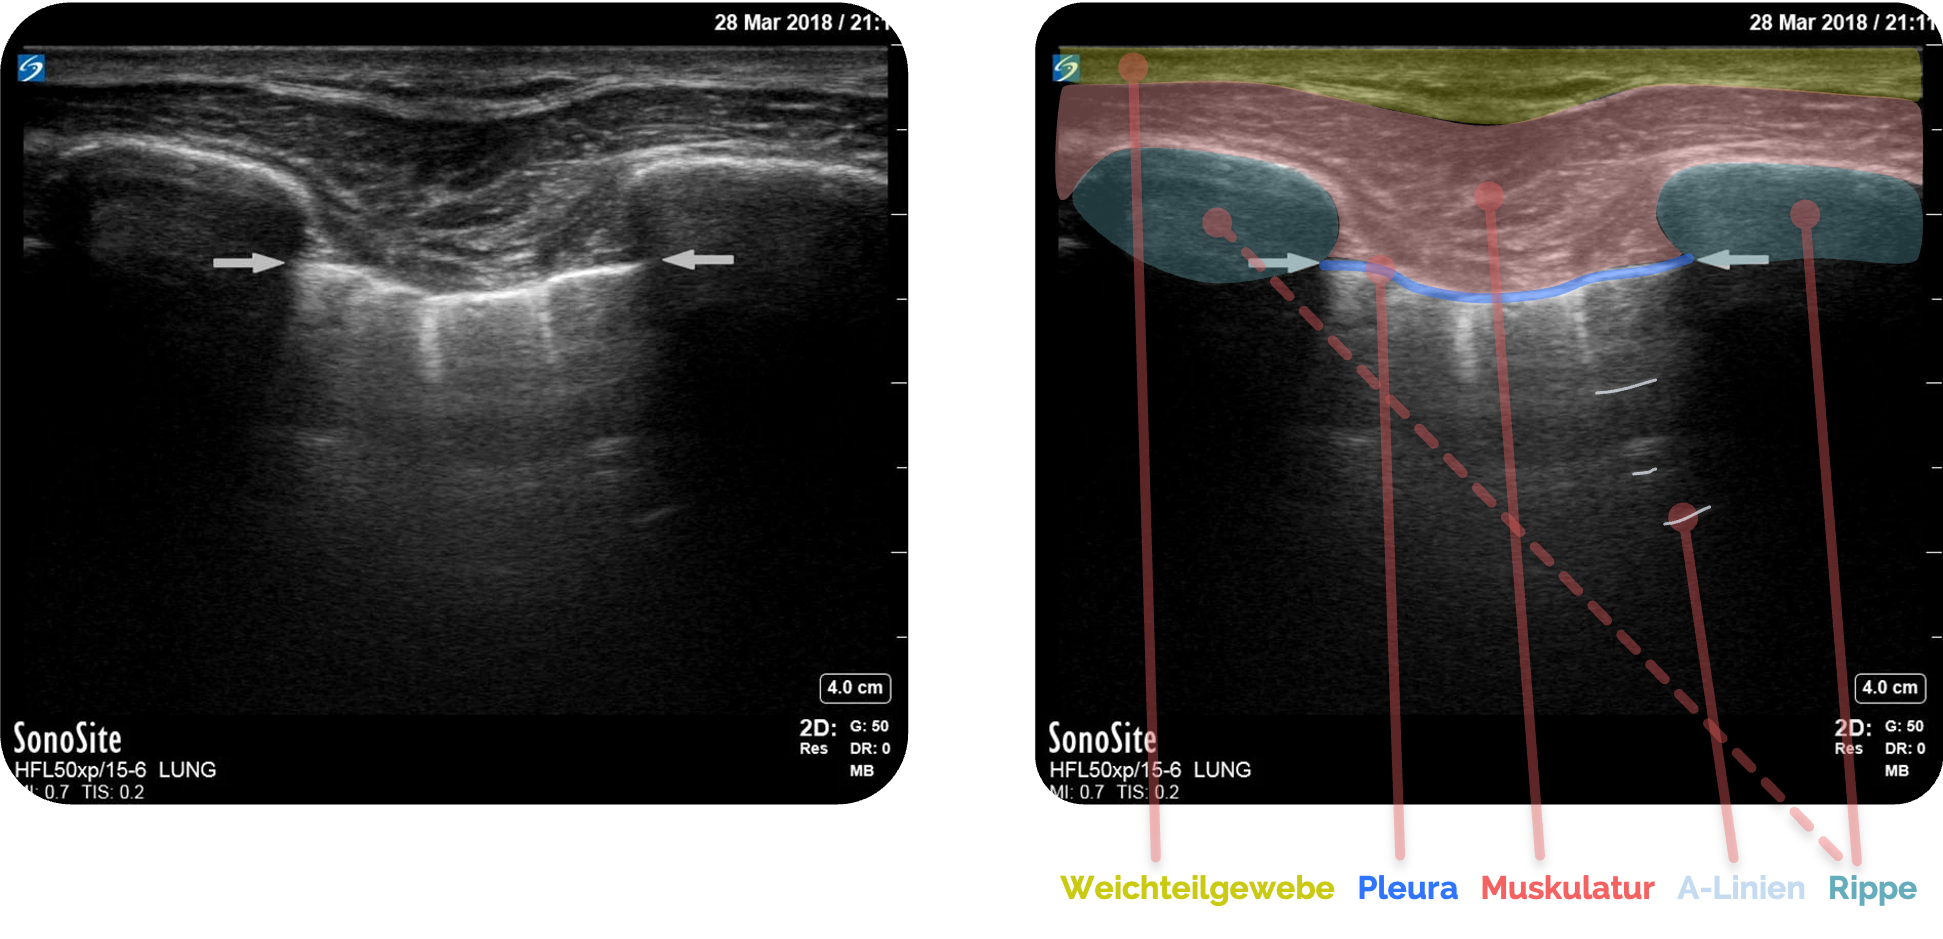

Schritt 2: Anatomische Leitstrukturen - Orientierung

- Oberflächliches Weichteilgewebe und Interkostalmuskulatur

- Rippen

beidseits rechts und links als echoreiche, gebogene Konturen mit Schattenbildung - Dazwischen die Pleuralinie als glatte, echoreiche horizontale Linie (siehe roter Pfeil)

Figure 1 aus Ketelaars, R., Reijnders, G., van Geffen, GJ. et al. ABCDE of prehospital ultrasonography: a narrative review. Crit Ultrasound J 10, 17 (2018). https://doi.org/10.1186/s13089-018-0099-y. Teilausschnitt des Originalbilds. Es wurden die Beschriftungen und der rote Pfeil hinzugefügt.

Sonographisch erscheint die Pleura als helle, echoreiche Linie zwischen den beiden Schallschatten

Der Nachweis einer intakten Pleura ergibt sich aus der Verschieblichkeit der Pleura parietalis

Direkt unter der Pleura ist typischerweise ein feines, artefaktbedingtes Streifenmuster sichtbar, die sogenannten A-Linien, die horizontal und regelmäßig verlaufen. Sie entstehen durch Mehrfachreflexionen an der luftgefüllten Lunge

Figure 1 aus Ketelaars, R., Reijnders, G., van Geffen, GJ. et al. ABCDE of prehospital ultrasonography: a narrative review. Crit Ultrasound J 10, 17 (2018). https://doi.org/10.1186/s13089-018-0099-y. Teilausschnitt des Originalbilds. Es wurden teilweise die Markierungen und Beschriftungen ergänzt.